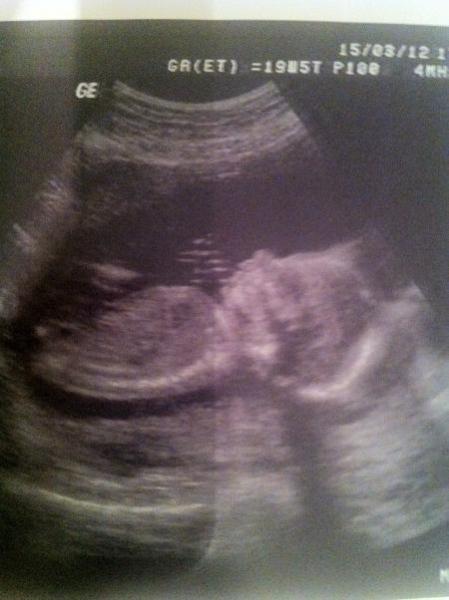

Guten Morgen Ihr Lieben, danke für das Daumendrücken, es halt geholfen! Mit meinem Mini ist alles ok. Kopfumfang 16 cm ein zierliches, Köpfchen aber im Normalbereich - ganz die Mama hab auch einen kleinen Kopp ! Es ist 20 cm insgesamt groß bzw. klein. Alles normal entwickelt! Hat geschlafen und dann als der Doc ein bisserl gerüttelt hat, hat es gezappelt und am Daumen gelutscht... sweet ! Habe den Doc dann gefragt, ob er sehen kann, was es wird! Da meinte er nur: "Ach, Sie wollten es wissen?" So ein Schelm ! Hat dann genauer geschaut und hat mir gesagt, dass es zu 99% ein wird! Hab fast geheult und mich so gefreut! Hab es dann auch gesehen, da er es rangezoomt hat ;-))! War danach shoppen, werdender Papa und Eltern, Schwiegermama berichten und dann mit meiner Schwester was essen, deshalb schreibe ich jetzt erst ! Wünsche Allen ein schönes,sonniges Weekend ! LG Mone PS: Bildchen kommt gleich ...

so Bildchen ... von meinem Mädel ... hoffe man erkennt was :-))